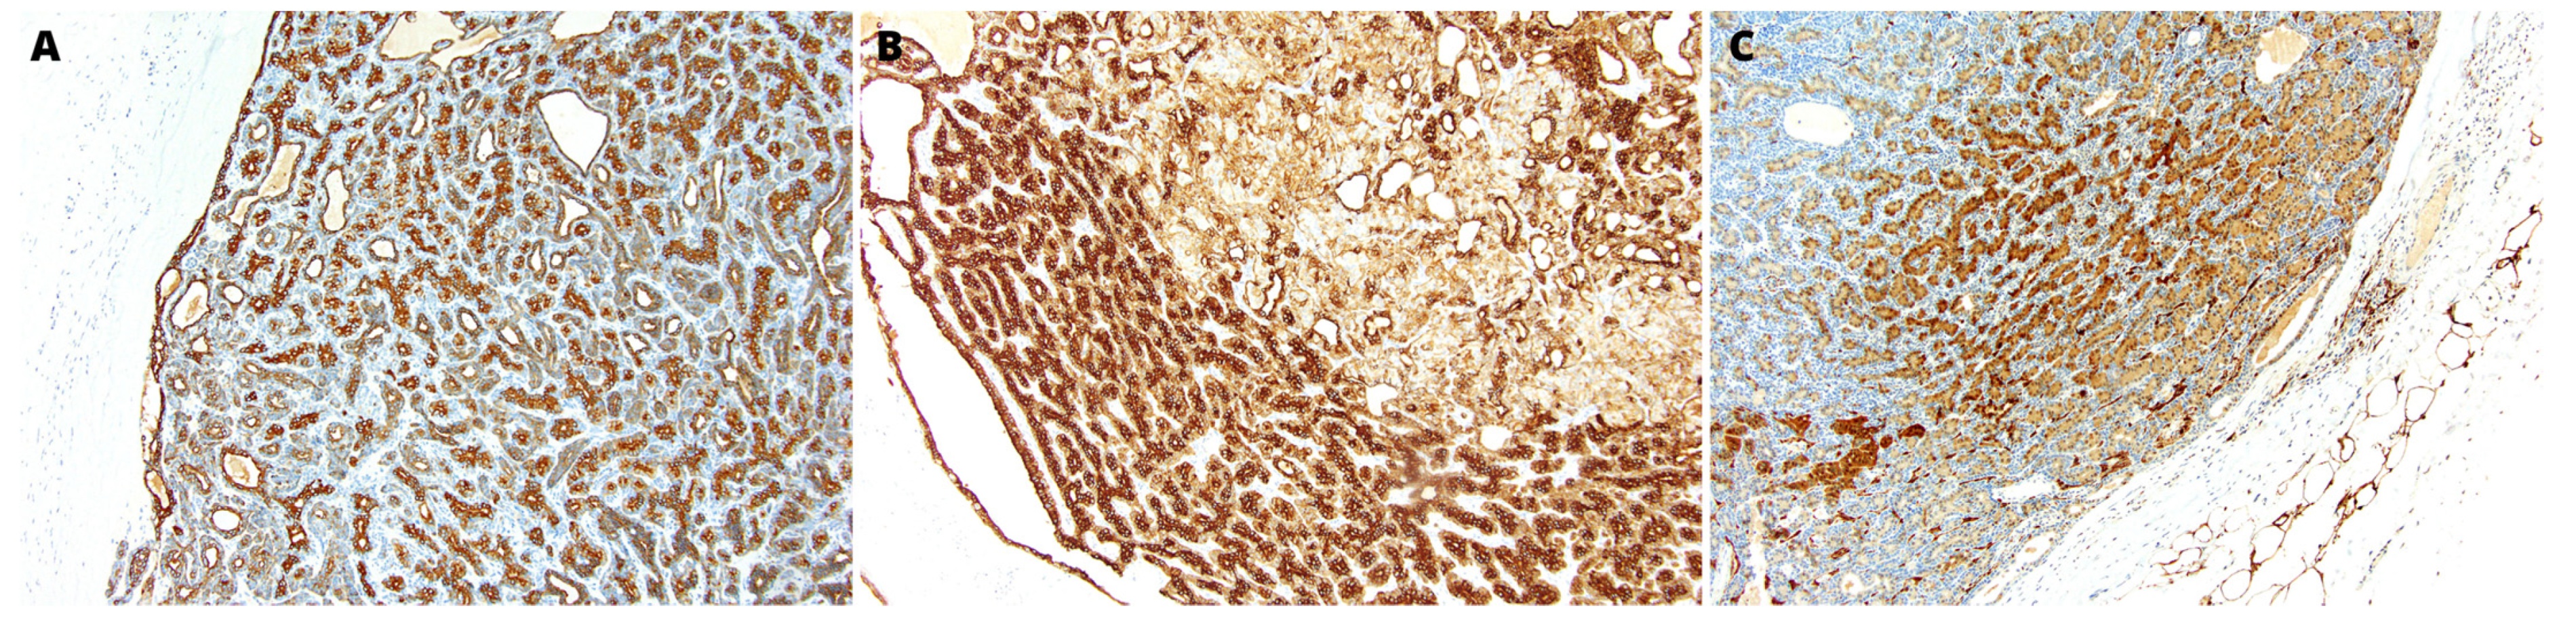

2.2. Pathology